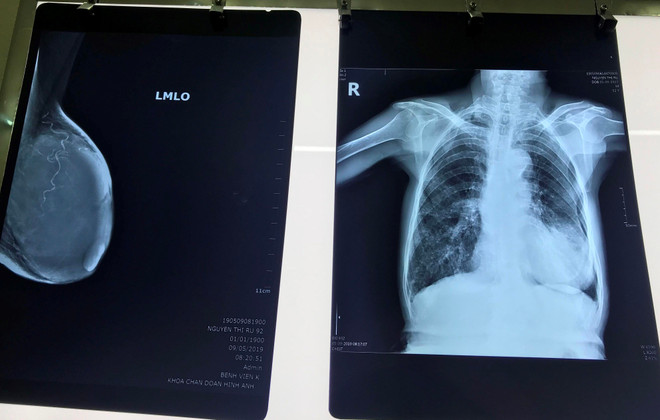

Phẫu thuật thành công điều trị ung thư vú cho cụ bà 92 tuổi ảnh 1Phim chụp khối u của bệnh nhân. (Ảnh: PV/Vietnam+)

Sau khi các bác sỹ thăm khám, chụp chiếu, kết quả cho thấy khối u kích thước 10x6cm chiếm toàn bộ vú trái bệnh nhân, được chẩn đoán ung thư vú giai đoạn tiến triển.